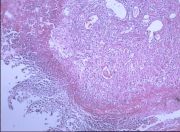

| 2021年12月10日 (五) 13:22 | 24号切片-小叶性肺炎-镜下观1.jpg (文件) |  |

145 KB | Cirno.9 | 基于MsUpload的文件上传 | 1 |